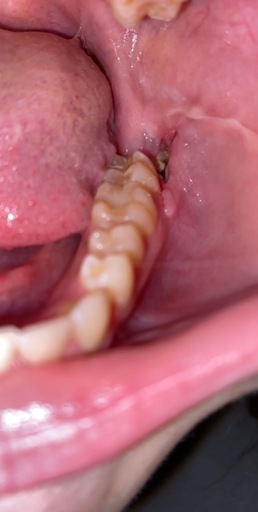

Hello! Im 15 and i have a impacted canine that is growing sideways and i still have a baby tooth. Can i get the adult tooth removed and have my baby tooth look like my other adult canine that came in? I do not want braces for a single tooth. I would not mind keeping the baby tooth if it could look like my other canine